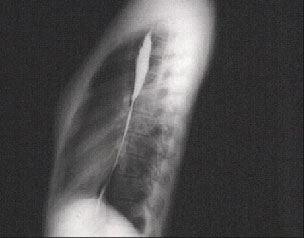

The lateral X ray with barium swallow shown here clearly demonstrates the reduced anteroposterior dimension with a loss of dorsal kyphosis that is, a straight back. And there is obliteration of the retrosternal space.

Because of this skeletal variation, the cardiac silhouette and pulmonary artery may appear to be enlarged in the PA chest X ray. Patients with this variation may present with an exaggeration of normal bedside findings and mitral valve prolapse may be associated with this syndrome.